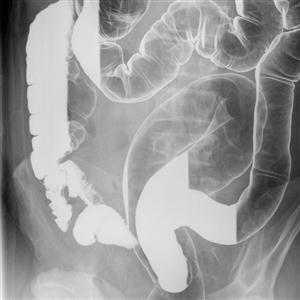

1)Barium Studies :

- c) Barium Enema (Mainly for large intestine) In Children and Adults.